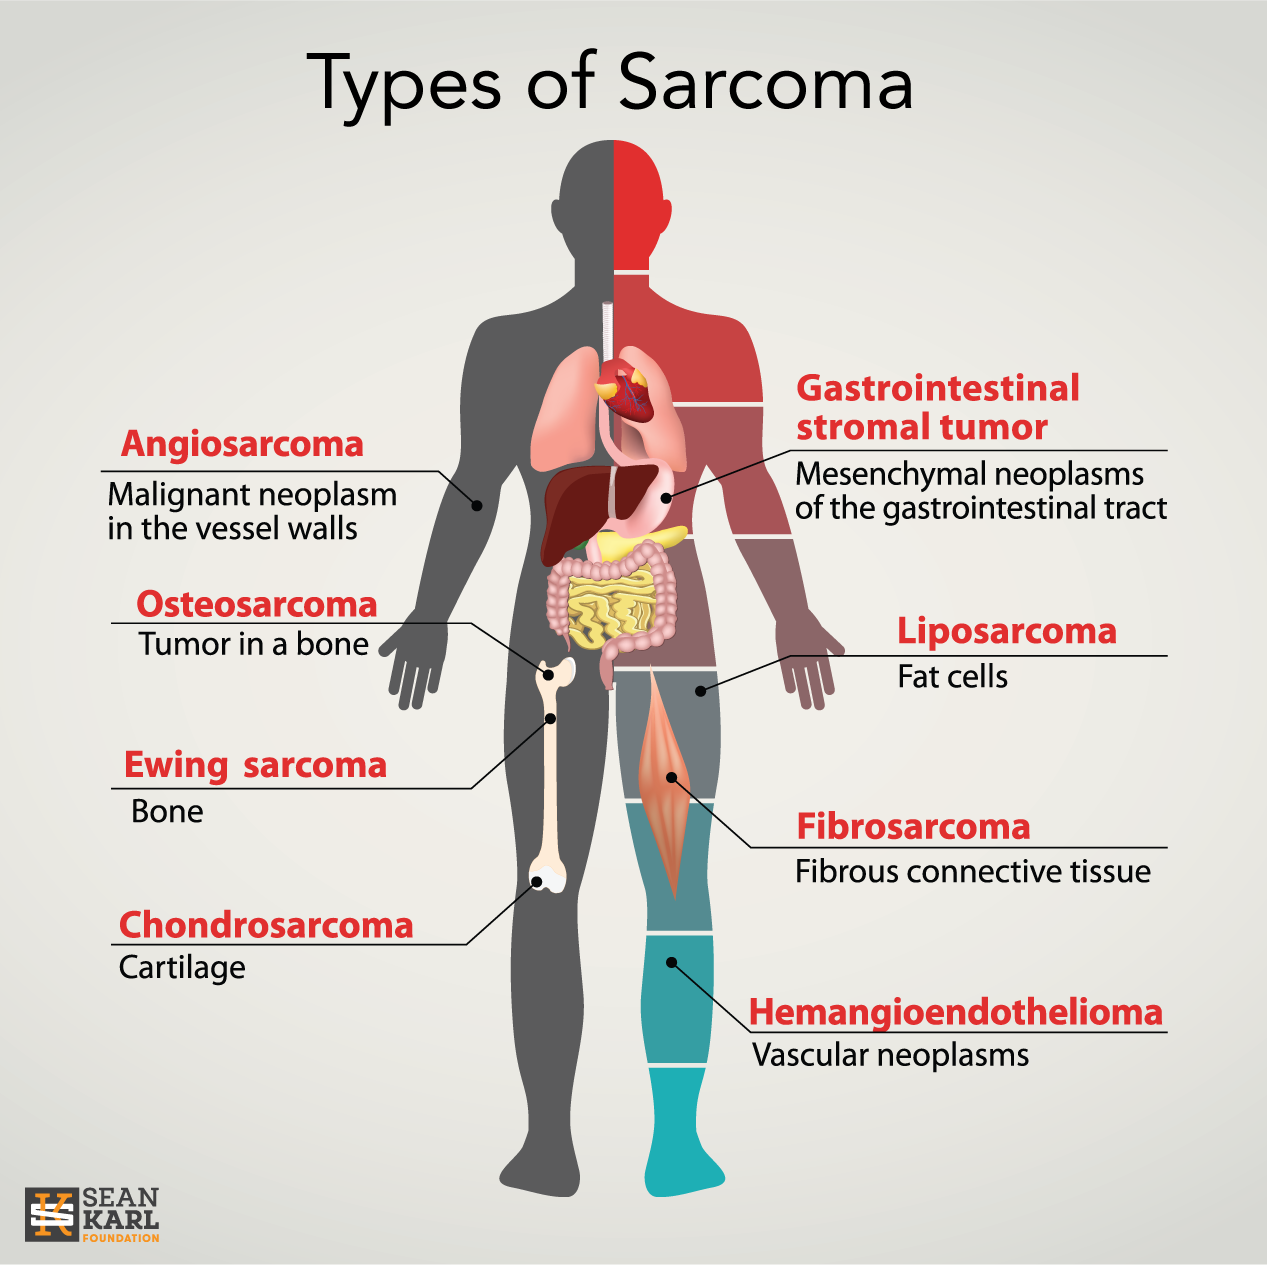

https://seankarlfoundation.org/wp-content/uploads/sarcoma-types.png